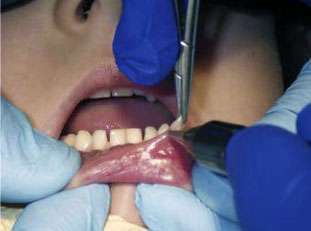

Initial findings: A painless, raised, well circumscribed, semitranslucent, confined lesion 5mm in diameter was located on the patient’s lower lip (Figs. 2 and 3). The 5-year-old patient was otherwise healthy. The lesion had been present for four months; the patient’s parents requested that it be removed.

Diagnosis and treatment plan: The lesion was clinically diagnosed as an extravasation mucocele; no histopathological analysis was needed. The proposed treatment plan was surgical excision using a CO2 10,600nm soft-tissue laser.

CO2 laser surgery: The lesion was excised with the CO2 laser. Local anesthetic (18 milligrams Septocaine and a 30-gauge needle) was used around the periphery of the lesion. To start, the mucocele was pulled upward with forceps to create tension (Fig. 4). The laser was then used to remove the lesion in two sections. The handpiece was held perpendicular to the target tissue to facilitate cutting. The first section of the lesion was larger (Figs. 4–6). The second was hidden beneath the top section (Fig. 8). Fluid was released and there was immediate hemostasis with minimal bleeding. The postoperative site was treated with a defocused beam (Fig. 9) for enhanced surface hemostasis and coagulation. The procedure took less than one minute to complete.